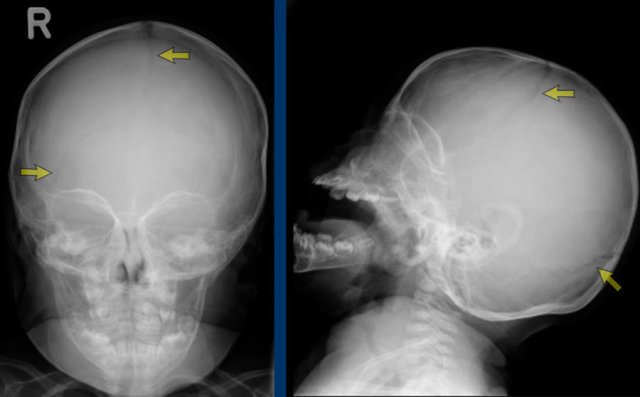

Scaphocephaly means ‘boat shaped’ skull and results from a premature closure of the sagittal suture (arrow).

The skull is narrow and long.

It is the most common monosutural craniosynostosis.

Sometimes it is called dolichocephaly, as ‘dolicho’ means long.

Images

Scaphocephaly: The head has a short laterolateral and a long anteroposterior diameter.

Trigonocephaly refers to the triangular head form resulting from premature closure of the metopic suture (arrows).

Physiological closure can already start as early as three months of age, so premature closure typically presents early.

The frontal head volume is small with a pointy forehead and hypotelorism.

Only pronounced cases require surgery and if there is clinically no indication for surgery, a CT is not needed.

Trigonocephaly: Pointy forehead and hypotelorism. Seen from above the lateral orbital rim will be visible.